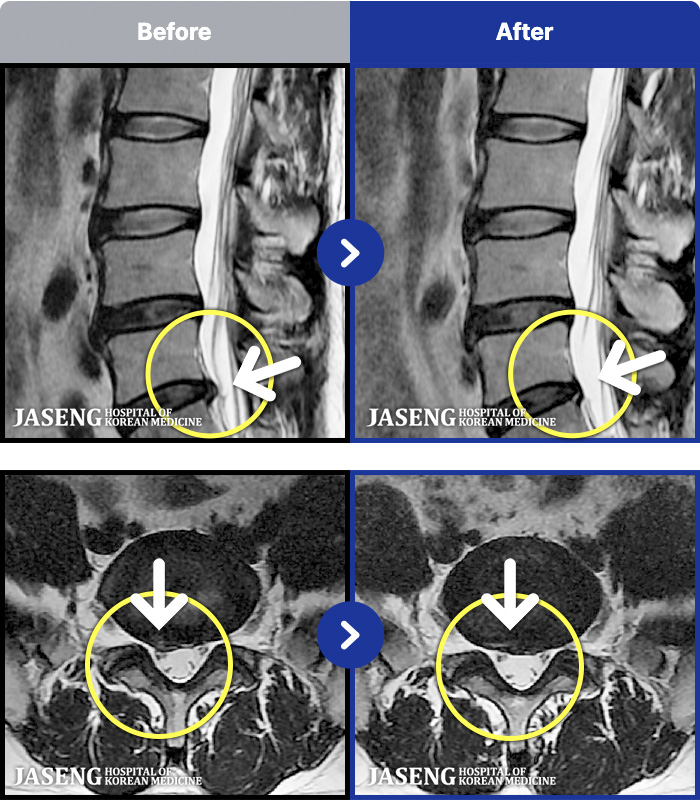

1,286 MRI ũ ʸ Ȯϼ.

ȯںп Ǹ ǿ ԿǾ, ο ġ ۿ Ƿ ġḦ Ͻñ ٶϴ.